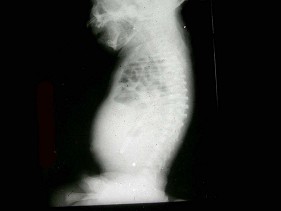

男,2岁,关节肿胀,结合图像,最可能的诊断是()

44、单项选择题 下述肺淀粉样变性胸部影像,错误的是()

C.向足侧倾斜35°~45°

D.向足侧、面侧各倾斜15°

E.向头侧倾斜35°~45°

98、多项选择题 多发性骨软骨瘤出现哪些情况应高度怀疑恶变()

A.软骨帽增厚,发生于长骨者超过1cm

B.钙化软骨帽密度变淡,边界不清

C.瘤体内出现透亮区

D.远处出现转移性病灶

E.30岁以上的患者肿瘤体积突发性增大